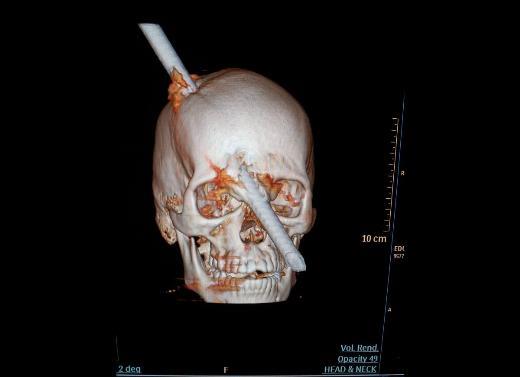

16. Bu tomografi görüntüsü ise 24 yaşında bir inşaat işçisi olan Eduardı Leite'ye ait. Kafasının üstünden girip gözünün hemen yanından çıkan metal parçasıyla kafası parçalanan genç adam, beş saatlik bir operasyon sonucu kafasındaki metal parçadan kurtarılmıştı.

Bu tomografi görüntüsü ise 24 yaşında bir inşaat işçisi olan Eduardı Leite'ye ait. Kafasının üstünden girip gözünün hemen yanından çıkan metal parçasıyla kafası parçalanan genç adam, beş saatlik bir operasyon sonucu kafasındaki metal parçadan kurtarılmıştı.